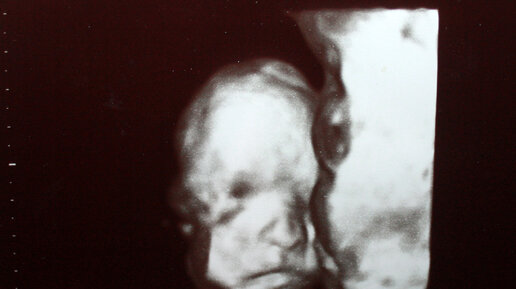

Как выглядит мальчик на всех скринингах узи.☺️

"Отличный пацан", сказал врач в 20 недель на узи

Как и положено после второго узи мы с мужем узнали, что ждём мальчика, он, конечно, был очень рад, ведь девочка у нас уже есть, а теперь ещё скоро будет сын. Омрачало только наличие предлежания плаценты. В женской консультации после второго узи диагноз “краевое предлежание” подтвердили и успокоили, что обычно ближе к родам плацента поднимется и можно даже будет рожать естественным путем. На самом деле, в большинстве случаев так и бывает, во втором и третьем триместре плацента потихоньку поднимается и никакой опасности во время самой беременности не представляет...